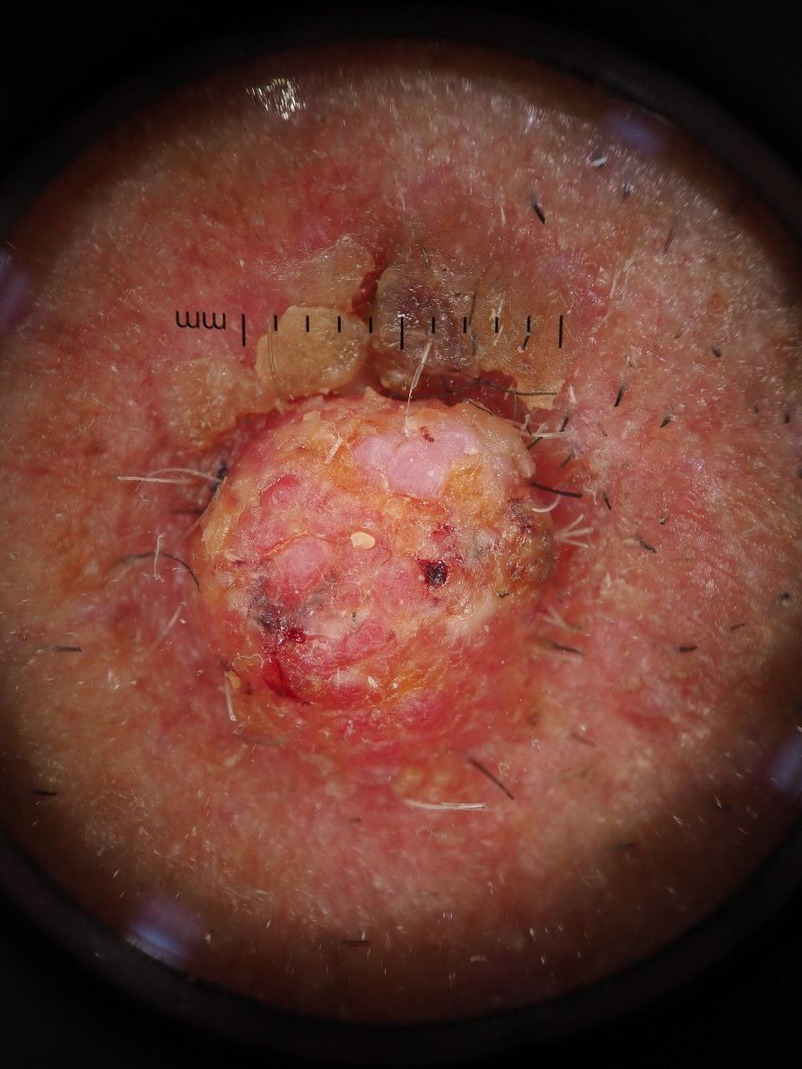

Paramount Skin Check offers professional, in-person skin assessments using advanced imaging technology to detect early signs of skin cancer and other skin conditions.

Each case is reviewed by a fully licensed consultant dermatologist, ensuring that your results are based on expert clinical judgment—not just algorithms.

we believe that early detection requires the eyes and experience of real specialists who understand the subtle warning signs that machines may miss. Within 48 hours,